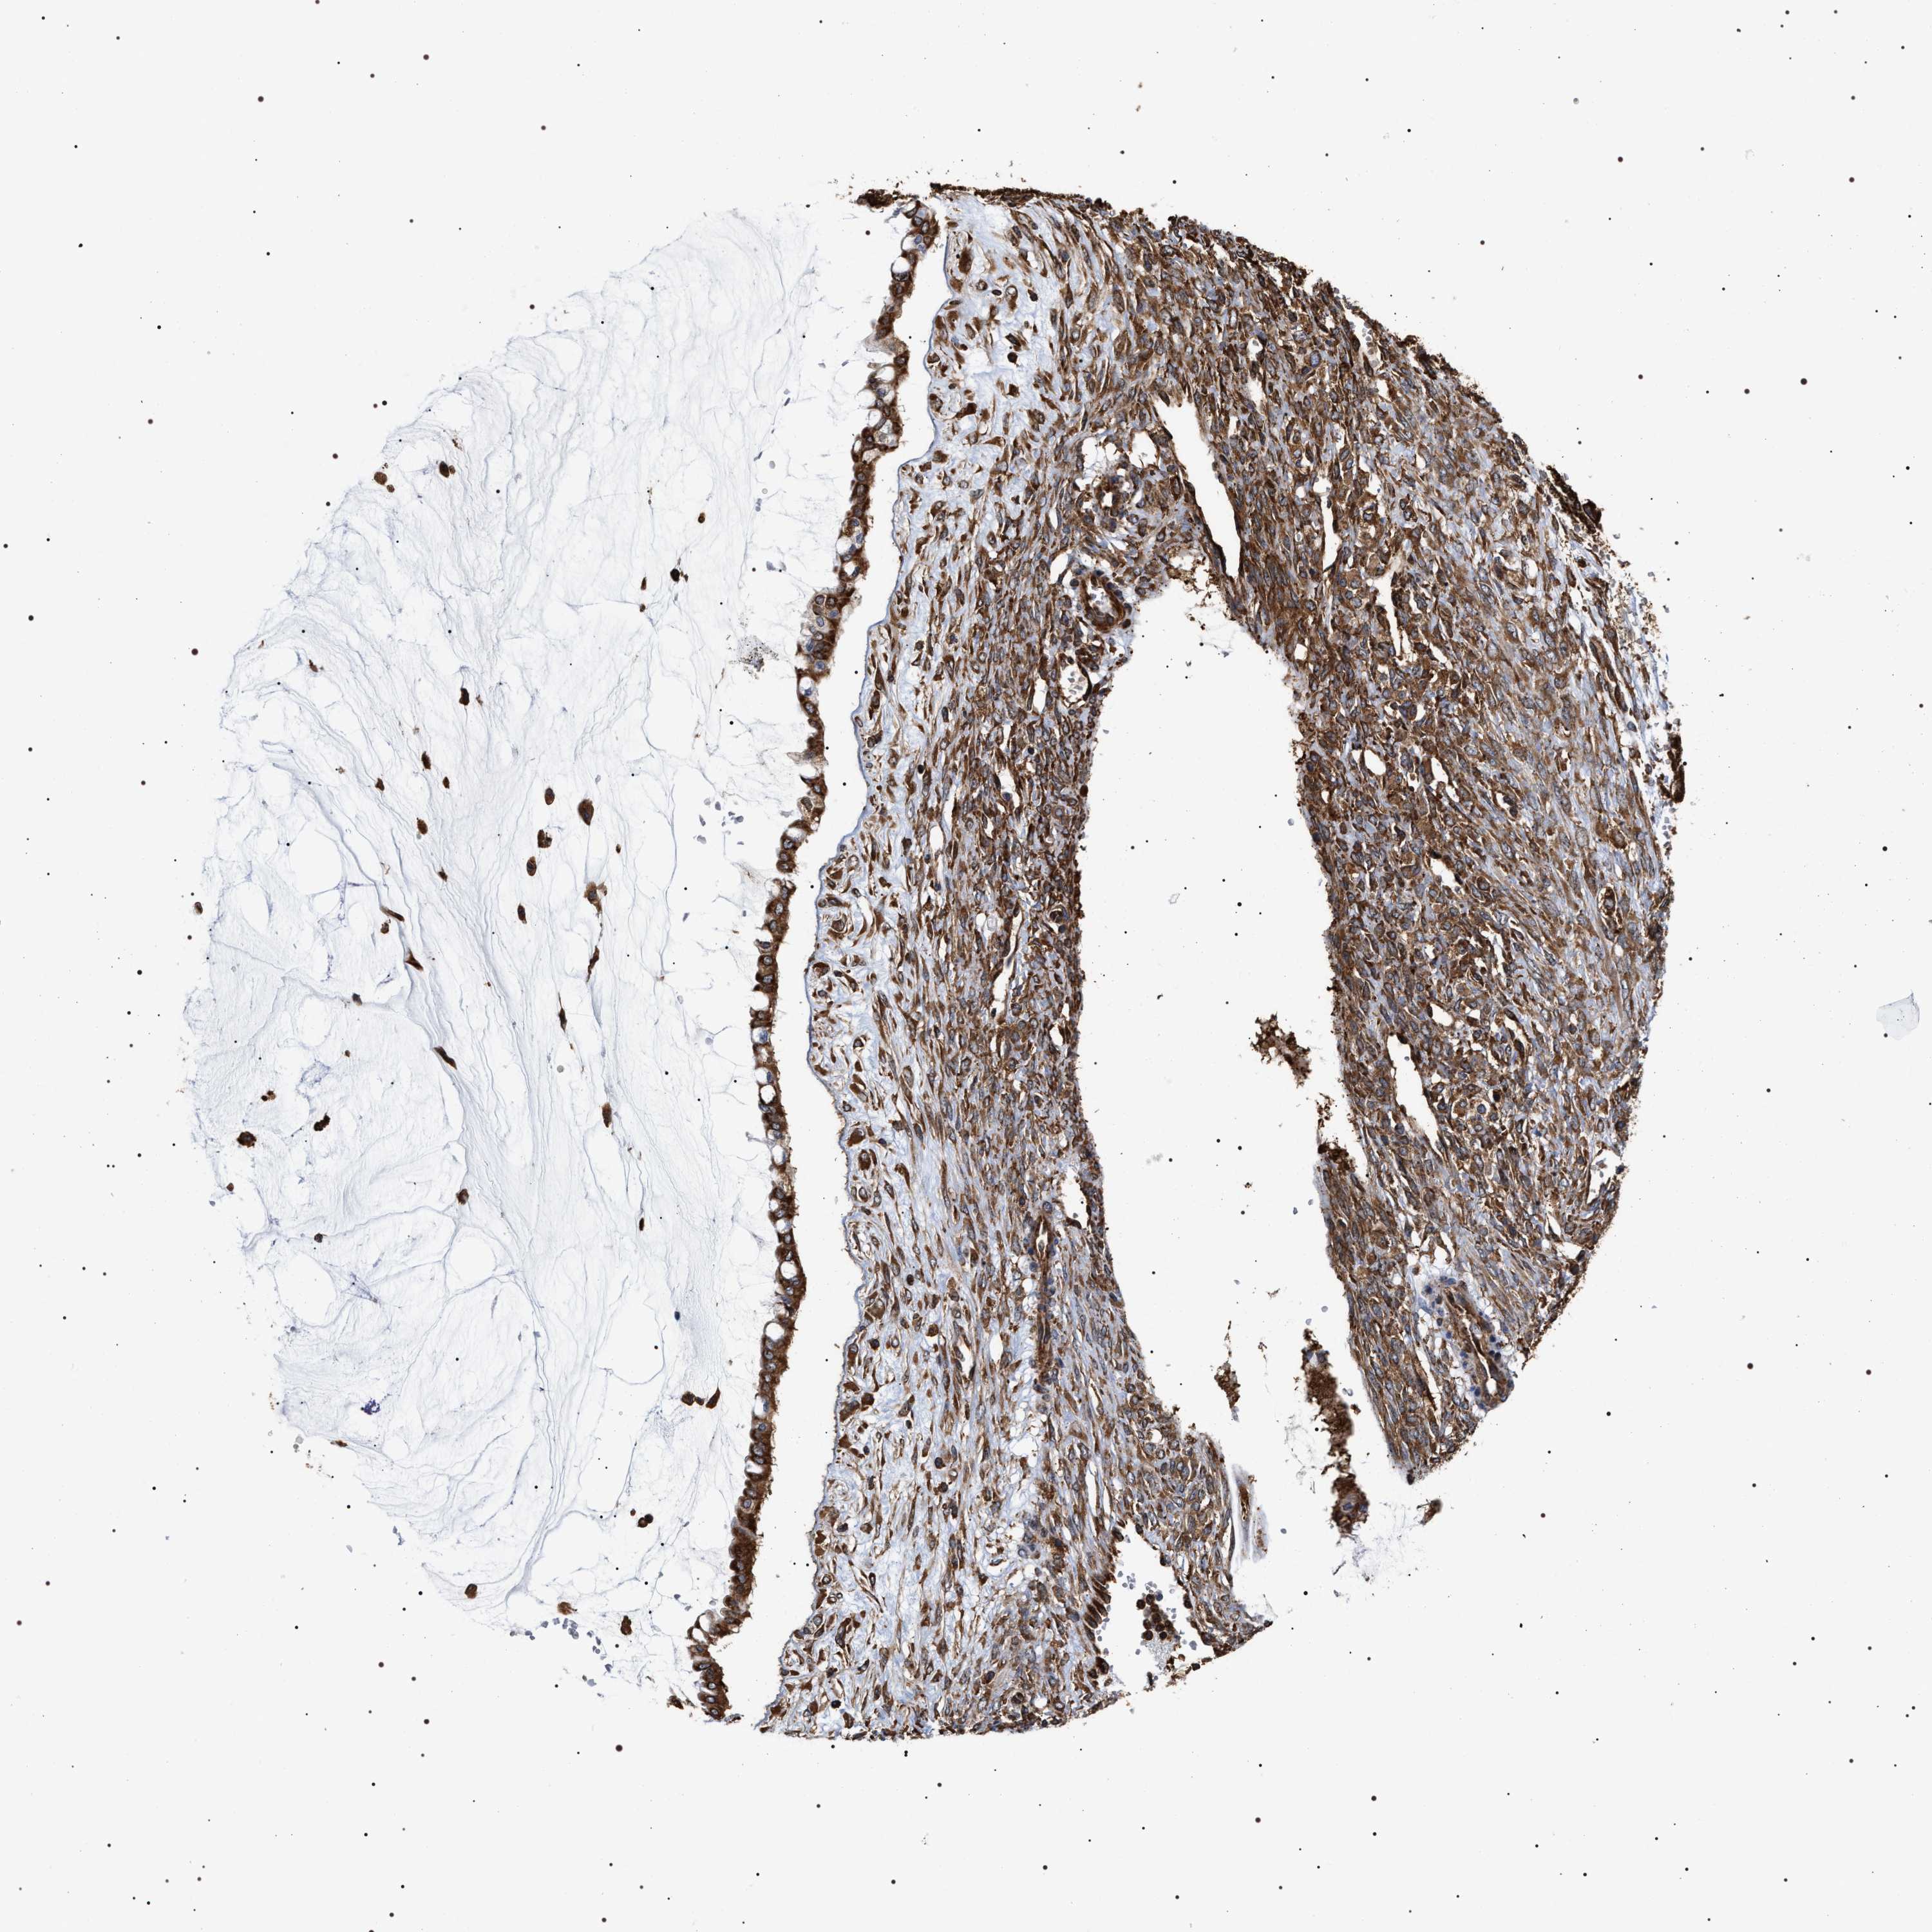

OVARIAN CANCER - Protein expressioni

A mouse-over function shows sample information and annotation data. Click on an image to view it in a full screen mode. Samples can be filtered based on level of antibody staining by selecting one or several of the following categories: high, medium, low and not detected. The assay and annotation is described here.

Note that samples used for immunohistochemistry by the Human Protein Atlas do not correspond to samples in the TCGA dataset.

Antibody stainingi

Antibody staining in the annotated cell types in the current human tissue is reported as not detected, low, medium, or high, based on conventional immunohistochemistry profiling in selected tissues. This score is based on the combination of the staining intensity and fraction of stained cells.

Each image is clickable and will lead to virtual microscopy that enables deeper exploration of all samples and also displays staining intensity scores, fraction scores and subcellular localization as well as patient and tissue information for each sample.

Antibody HPA020559

Antibody CAB026297

Staining

High

Cystadenocarcinoma, serous, NOS